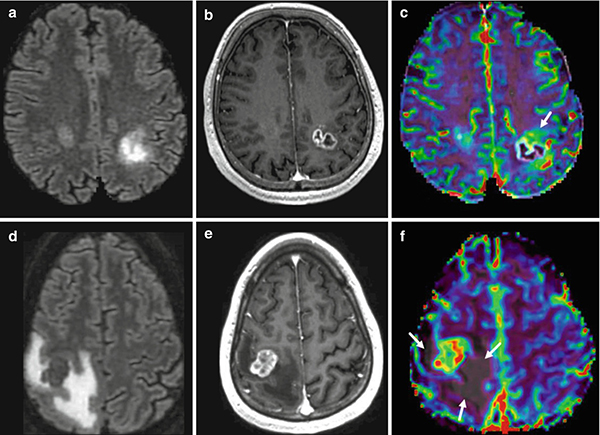

МРТ головы с контрастным препаратом позволяет выявить различные патологические процессы на начальных этапах развития, что исключает вероятность осложнений. Диагностическая процедура дает намного больше информации, чем другие исследования. МРТ с контрастом отличается высокой информативностью и достоверностью.

Принцип МРТ головы заключается в осуществлении магнитного воздействия на организм для получения трехмерного изображения определенного участка. Отличие от стандартного метода диагностики заключается во введении контрастного вещества, повышающего информативность и четкость получаемого изображения.